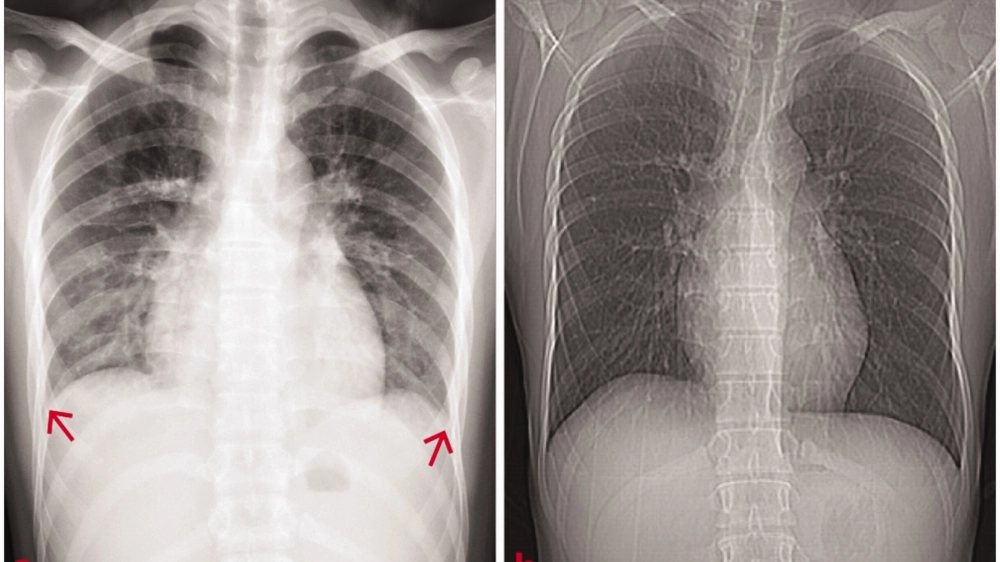

Các triệu chứng chính của bệnh viêm cầu thận cần chú ý

• Phù là triệu chứng rất điển hình, thường xuất hiện ở mặt (mí mắt) vào buổi sáng, sau đó có thể phù toàn thân, kèm theo tăng huyết áp.

Hình ảnh phù nề ở mặt và chân do viêm cầu thận